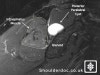

상견갑신경이 상견갑 절흔(suprascapular notch)라는 아주 좁은 골목을 지나게 되는데 하필 이 주위에 무슨 병변이 생겨서 특히 MRI에 보이듯이 어깨 부위에 생긴 결절종이 이 신경을 눌리게 되어 극하근(가끔은 극상근)이 위축되는 증상을 보이게 됩니다.

초기 진단의 단서는 극하근의 위축된 것을 발견하는 것이며, 상견갑 절흔 주위에 압통이 있다면 의심할 수 있습니다. 근전도를 시행하고 MRI를 통해서 병변을 확인하게 됩니다. 특히 팔을 많이 사용하는 사람들의 부위가 불명확한 통증이 있을 때 의심해 볼 수 있습니다. 상대적으로 발달된 근육을 보이는 삼두박근이나 삼각근에 비해 극상근과 극하근이 매우 위축된 것을 볼 수 있습니다.